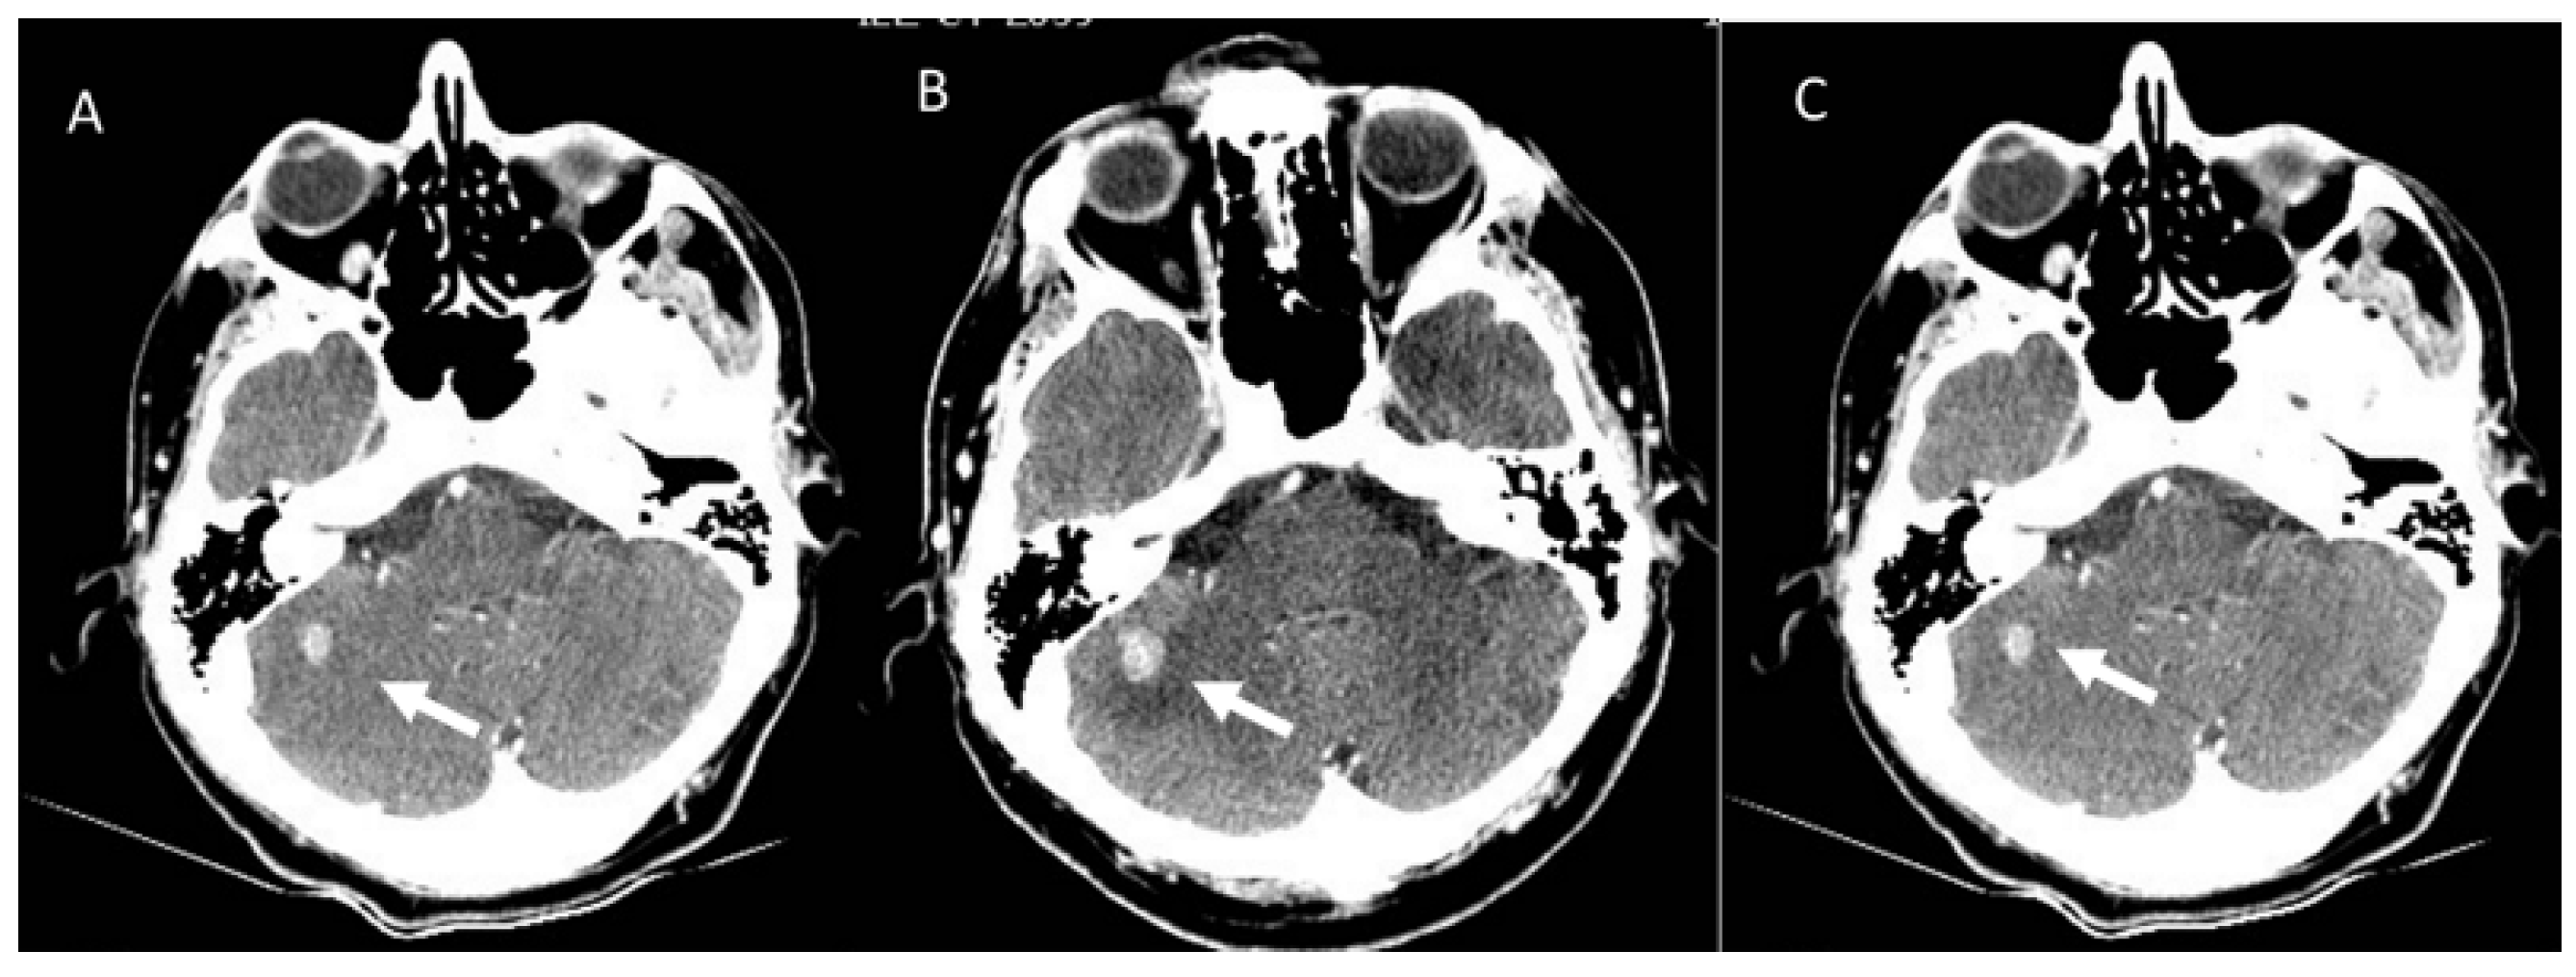

- Comstock, D.E.; Nishino, M.; Giardino, A.A. Headache in the setting of immunotherapy treatment for metastatic melanoma. JAMA Oncol. 2017, 3, 703–704. [Google Scholar] [CrossRef]

- Faje, A.T.; Sullivan, R.; Lawrence, D.; Tritos, N.A.; Fadden, R.; Klibanski, A.; Nachtigall, L. Ipilimumab-induced hypophysitis: A detailed longitudinal analysis in a large cohort of patients with metastatic melanoma. J. Clin. Endocrinol. Metab. 2014, 99, 4078–4085. [Google Scholar] [CrossRef]

- Min, L.; Hodi, F.S.; Giobbie-Hurder, A.; Ott, P.A.; Luke, J.J.; Donahue, H.; Davis, M.; Carroll, R.S.; Kaiser, U.B. Systemic high-dose corticosteroid treatment does not improve the outcome of ipilimumab-related hypophysitis: A retrospective cohort study. Clin. Cancer Res. 2015, 21, 749–755. [Google Scholar] [CrossRef]

- Kwak, J.J.; Tirumani, S.H.; Van den Abbeele, A.D.; Koo, P.J.; Jacene, H.A. Cancer immunotherapy: Imaging assessment of novel treatment response patterns and immune-related adverse events. Radiographics 2015, 35, 424–437. [Google Scholar] [CrossRef]

- Tirumani, S.H.; Ramaiya, N.H.; Keraliya, A.; Bailey, N.D.; Ott, P.A.; Hodi, F.S.; Nishino, M. Radiographic profiling of immune-related adverse events in advanced melanoma patients treated with ipilimumab. Cancer Immunol. Res. 2015, 3, 1185–1192. [Google Scholar] [CrossRef]